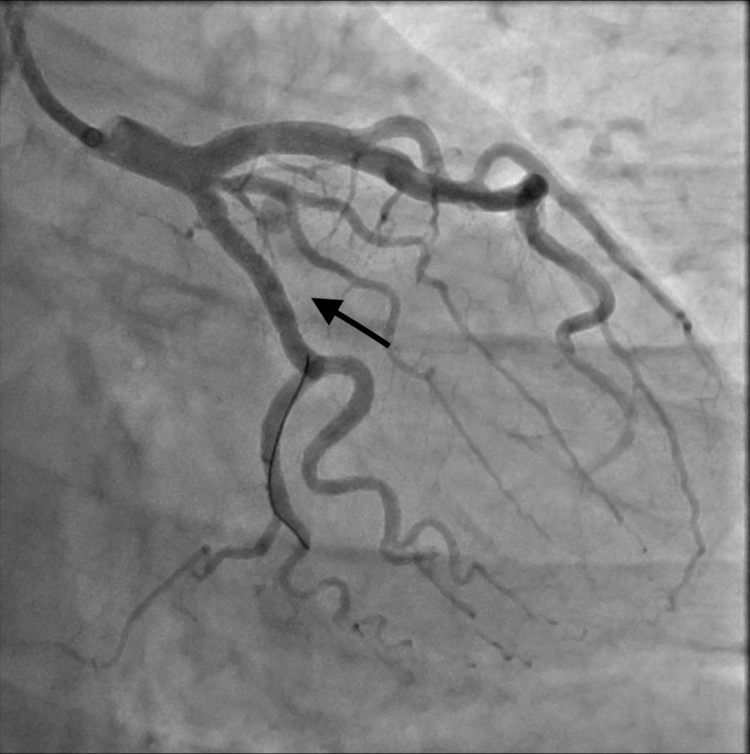

| Túi giả phình động mạch sau can thiệp - Ảnh BVCC |

Ngay sau ca can thiệp, bệnh nhân đỡ đau ngực, không còn khó thở và đã trở lại sinh hoạt bình thường. Bệnh nhân sẽ được chỉ định sử dụng thuốc kháng kết tập tiểu cầu, kiểm soát huyết áp, kiểm soát mỡ máu cũng như tái khám định kỳ.

Chính vì thế, chúng tôi đã tư vấn gia đình bệnh nhân và quyết định đặt 01 covered stent đoạn gần nhánh mũ chặn lỗ vào khối giả phình, giúp làm giảm nguy cơ vỡ giả phình trong tương lai cho bệnh nhân.”